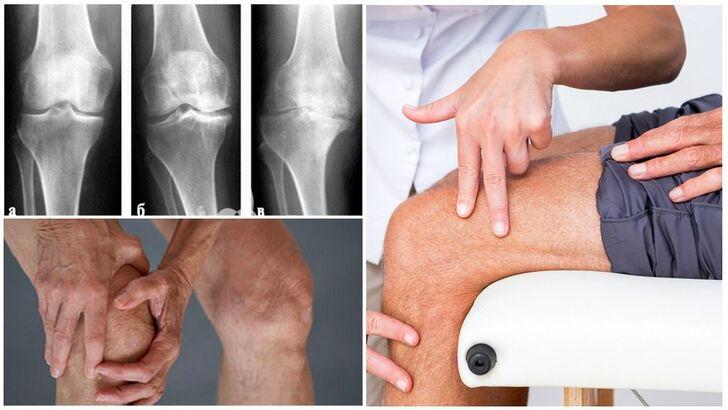

Наиболее часто используется классификация по рентгенологическим стадиям Kellgren-Lawrence.

В зависимости от выраженности клинических проявлений и изменений по данным лучевых методов обследования выделяют 3-4 стадии остеоартроза коленного сустава:

1. Начальная - незначительные клинические проявления, рентгенологические изменения минимальны

2. Умеренно выраженная - умеренный болевой синдром и нарушение функции сустава, рентгенологически определяется сужение суставной щели

3. Выраженная - постоянные боли, резкое ограничение подвижности в суставе, выраженные рентгенологические изменения в виде сужения суставной щели, кист и остеофитов

4. Терминальная - стойкие выраженные боли, значительное нарушение функции сустава вплоть до анкилоза, выраженные деструктивные изменения по данным рентгенографии

В зависимости от выраженности клинических проявлений и изменений по данным лучевых методов обследования выделяют 4 стадии остеоартроза коленного сустава:

1. Первая стадия (начальная) - незначительные клинические проявления, рентгенологические изменения минимальны

2. Вторая стадия (умеренно выраженная) - умеренный болевой синдром и нарушение функции сустава, рентгенологически определяется сужение суставной щели

3. Третья стадия (выраженная) - постоянные боли, резкое ограничение подвижности в суставе, выраженные рентгенологические изменения в виде сужения суставной щели, кист и остеофитов

4. Четвертая стадия (терминальная) - стойкие выраженные боли, значительное нарушение функции сустава вплоть до анкилоза, выраженные деструктивные изменения по данным рентгенографии

Таким образом, классификация с первой по четвертую стадию является наиболее распространенной.

Основным методом диагностики остеоартроза коленного сустава является рентгенография, позволяющая определить стадию заболевания.